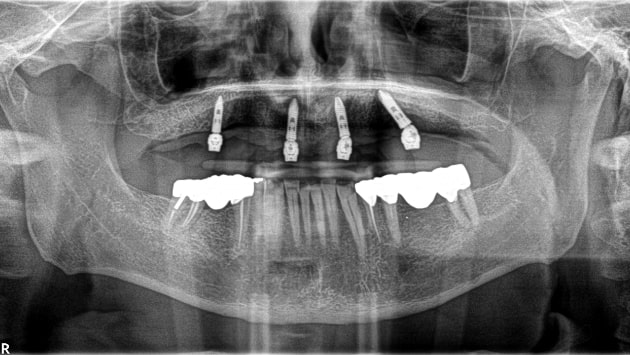

When patients are not candidates for All on 4 treatments

due to their medical conditions, 3 on 6 implants may be the

perfect solution. This procedure is considered one of the

best options for a full mouth restoration. It basically

consists of placing 3 zirconia bridges that are supported by

6 implants (two for each bridge.)

A specialist will evaluate your dental status using X-rays, panoramic photos of your mouth, a 3D CBCT scan, and other techniques to provide you with the best treatment options and suggestions.